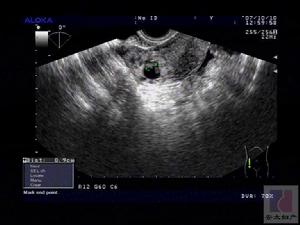

(三)B超、CT檢查及mri檢查

B超、CT檢查及mri檢查是臨床上最常採用的檢查方法,可確定腫塊的部位、大小、性質(如囊性或實性)與周圍組織的毗鄰關係等,但很少可以提示輸卵管來源。

輸卵管癌患者郭女士,54歲。婦檢:子宮前位,子宮正常大小,質中,無壓痛,宮頸光滑。左側附屬檔案可觸及約5.5cm×3cm大小包塊,右附屬檔案區未見異常。超聲檢查:子宮大小為4.8cm×3.5cm×4.1cm,包膜光滑,肌層回聲均勻,子宮內膜增厚,回聲稍增強,子宮左側見4.5cm×2.8cm的低回聲包塊,邊界清晰,形態為臘腸形欠規整,其內有回聲不均勻的低回聲改變。左側卵巢顯示不清。臨床診斷為:左側輸卵管癌治療:切除子宮及雙附屬檔案。術中見子宮正常大小,表面光滑。左側卵巢大小為2.0cm×1.8cm,左側輸卵管壺腹部明顯增粗、腫大,傘端封閉,形成大小為5.0cm×3.0cm臘腸樣腫塊,與周圍組織無明顯粘連,盆腔內未見腫大的淋巴結。右側附屬檔案未見異常。病理診斷結果:左側輸卵管低分化乳頭狀腺癌。經化療,情況良好。

⒊B型超聲掃描:可確定腫塊的部位、大小、性質及有無腹水等。